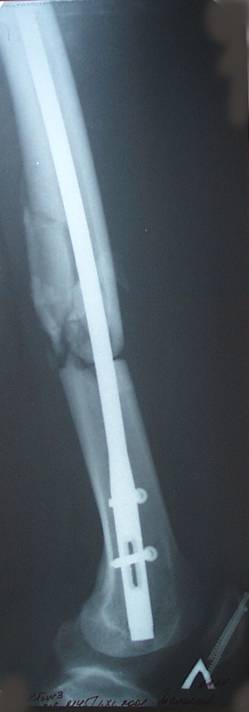

Уважаемый Сергей, избрав вариант DHS плюс ретроградный гвоздь Вы явно обезопасите себя от проблем, связанных с введением штифта через trochanteric fossa. Очень это может быть проблематично, Вы правы. Поэтому DHS плюс ретроградный гвоздь - спокойно выполнимый вариант, особенно в "чужом" отделении. Схожий свой случай из далёкого теперь уже 1999г. прилагаю, только вместо канюлированных винтов у Вас будет DHS (VHS). А если антеградный гвоздь - то только из тех, что предназначены к введению через верхушку вертела. И это тоже выполнимо, но сложнее. Мне так кажется.

Уважаемый Сергей Витальевич! Мы в похожем случае выбрали вариант DHS + DFN. Правда из 4 кортикальных винтов накладки DHS - 2 пришлось вводить монокортикально - уперлись в штифт.. На конечный результат это не повлияло. Ссылка здесь.